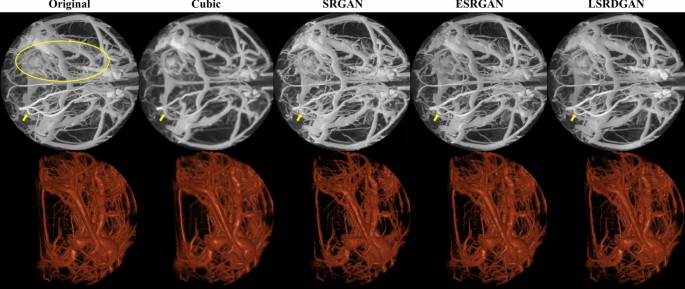

In addition, the proposed model trained without and with GAN also performed better on stroke data compared to others and generated a very similar image to the original HR image, as shown in Figs. 6 and 7, respectively. For further comparison, Supplementary Figs. 1 and 2 as well as Supplementary Animations 1 and 2 show generated images using PSNR-oriented models and PSNR and GAN–oriented models on HC data, respectively. In addition, Supplementary Figs. 3 and 4 as well as Supplementary Animation 3 also show a visual comparison of different models trained on HC data and applied to stroke data. In general, compared with the cubic spline interpolation, all deep learning models performed significantly better on both HC and stroke data.

Testing PSNR and GAN–oriented models on stroke data. The first row shows the HR and LR along with the SR data generated using PSNR and GAN–oriented models after maximum intensity projection in the sagittal direction. The second row shows volume-rendered data. The yellow ellipse on the original image shows the region of infarction due to ischemic stroke, and the yellow arrows show the visual difference of the vessel in the contralateral hemisphere, which appears occluded in the LR image.